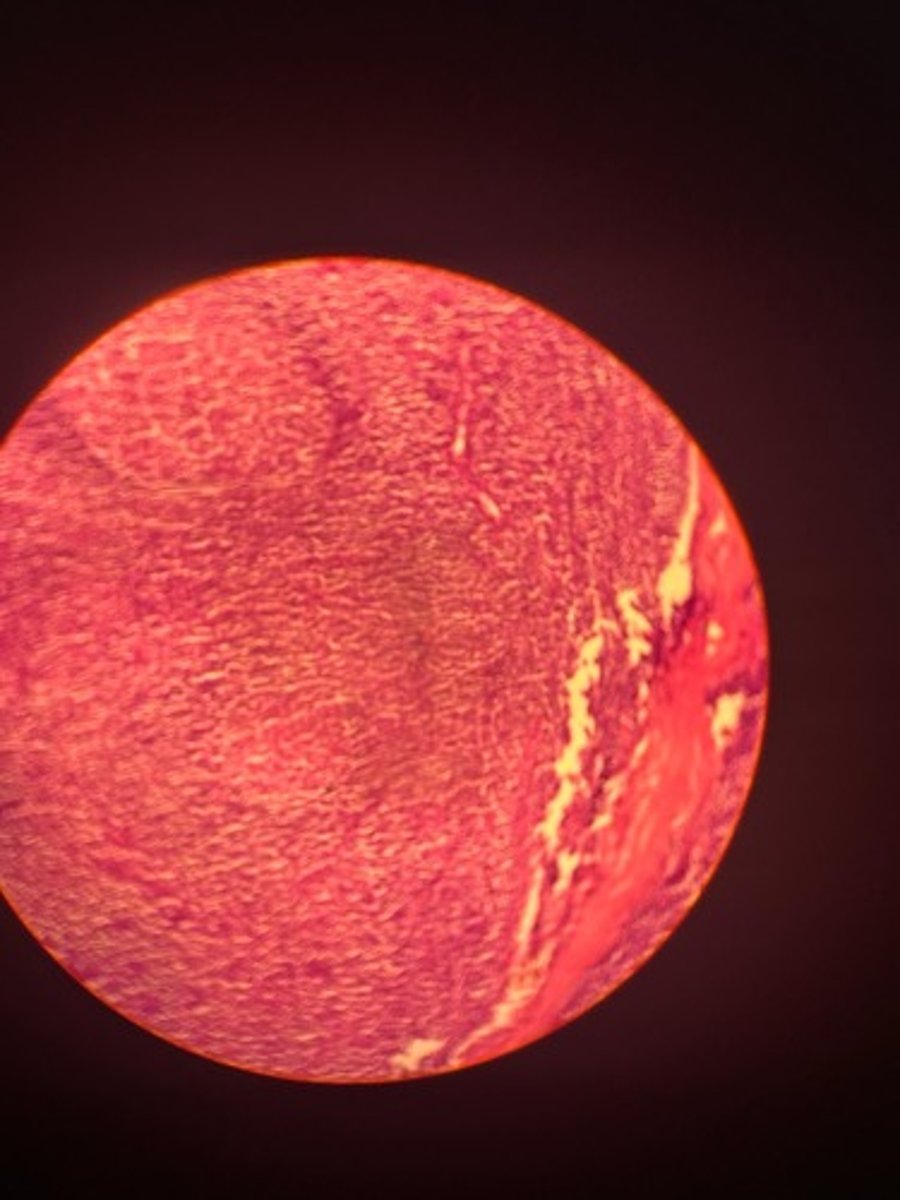

Tonsils HE

Tonsils HE

Tonsils HE